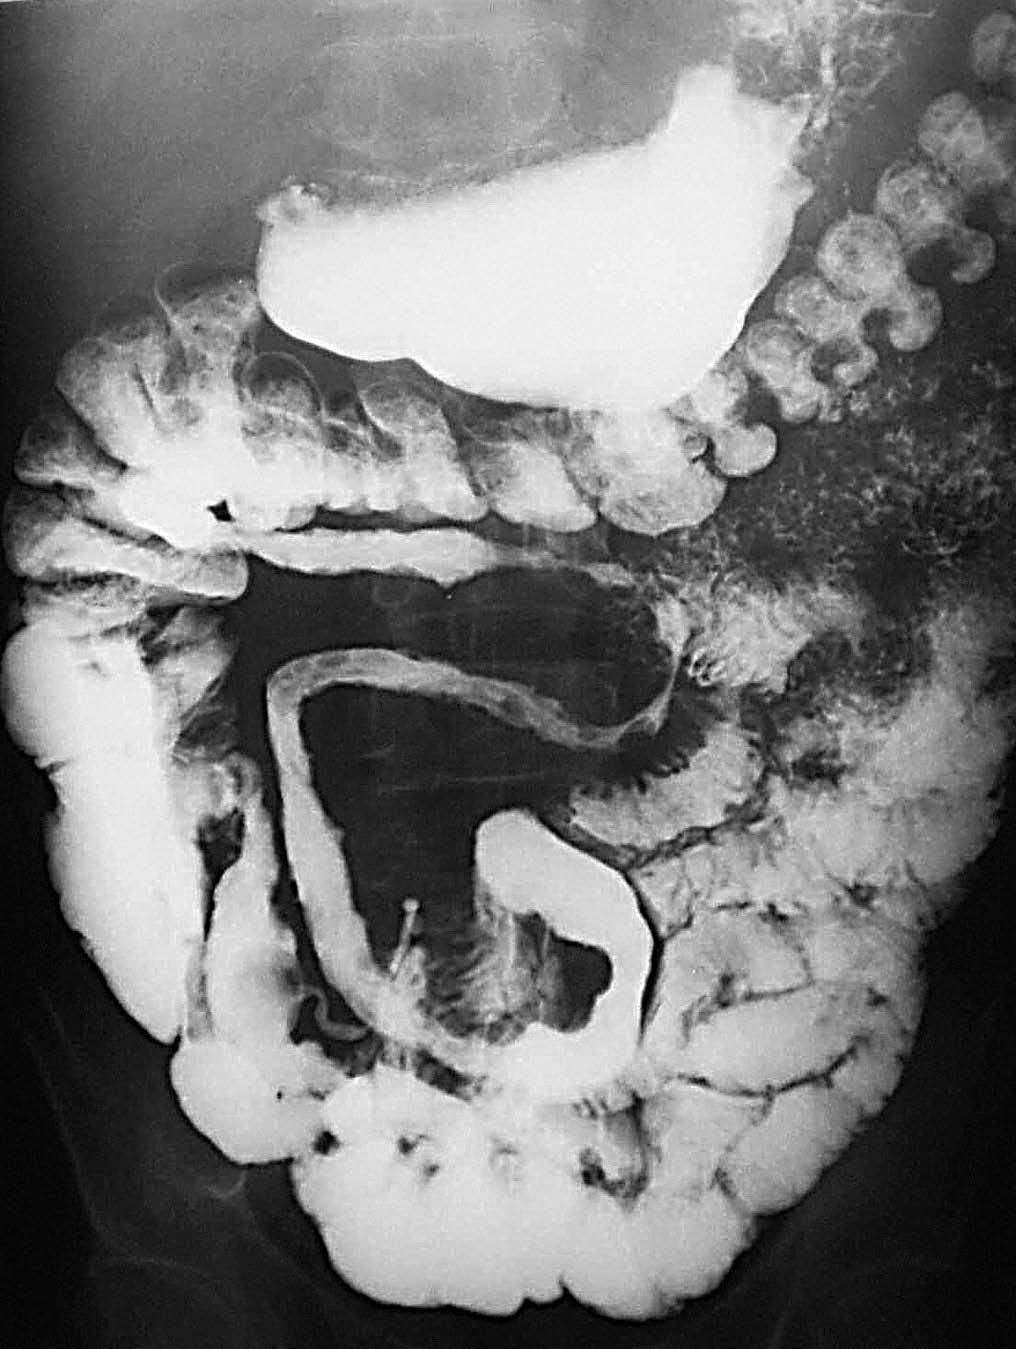

Existen situaciones en las que la EC está localizada exclusivamente a nivel del colon, colitis granulomatosa, hasta en un 19% de los casos. Esta situación plantea problemas de diagnóstico diferencial por imagen con otra entidad de distinto significado, pronóstico y tratamiento, como la CU.

Desde el punto de vista clínico hay ciertas diferencias con la CU, puesto que en la colitis granulomatosa no suele haber sangre en heces, no hay afectación rectal, la sigmoidoscopia, por ello, es normal aun cuando sí que son muy frecuentes las fístulas perianales y en general perirrectales. En contraposición, las manifestaciones extracolónicas son menos frecuentes que en la CU y tampoco suele presentarse la complicación de perforación libre del colon. A diferencia de la CU, la colitis granulomatosa no es curable con la colectomía e ileostomía u otra técnica que implique un reservorio ileal, por la tendencia de esta entidad a recurrir a dicho nivel.

Desde el punto de vista de los hallazgos radiológicos, éstos van a ser similares a los que ya hemos consignado. Pequeñas imágenes puntiformes de cúmulo de bario que corresponden a las úlceras aftoides, el patrón en "empedrado" por la desestructuración mucosa y la ausencia de afectación de la ampolla rectal son los hallazgos de imagen que cabe esperar en el estudio baritado.

Desde el punto de vista tomodensitométrico (fig. 12) y de la RM los criterios semiológicos son más o menos similares: el engrosamiento mural y la hiperemia característica de una situación inflamatoria activa. Se describe el hecho de que el engrosamiento mural del colon suele ser más marcado en la colitis granulomatosa que en la ulcerosa, lo mismo que la irregularidad de los contornos, que suele ser también más acentuada en los casos de colitis granulomatosa.